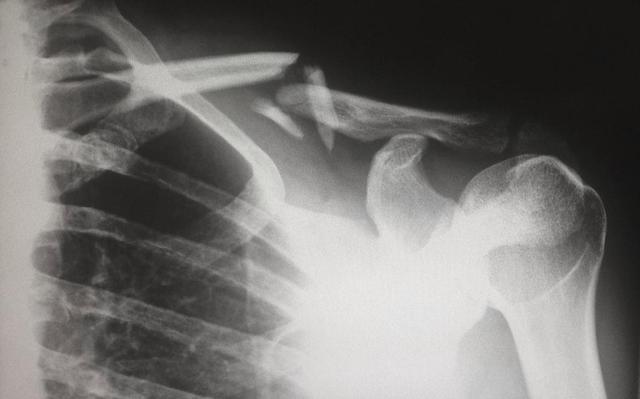

在回答是否要进行养骨的这个抉择前,先要做的,是应对自己来个简单的自测,以判断自身的骨骼还仍保持着健康的状态;在具体方法上,首先要先让自己站起来,保持双手叉腰的动作,接着将大拇指内藏,以食指靠肋骨底部,倘若末尾的小拇指碰不到盆骨,那么就说明骨骼大体健康,可如果小拇指碰到了盆骨,则脊柱便存在压缩、变形的可能。

一提到骨质疏松这个问题,其实并不如大家想的那般稀少,相反在中老年人群,尤其是四十岁以后的人群中,骨密度较低者占比已达35%左右,而知道自己存在骨密度较低问题,也即骨质疏松情况者,却不到1%